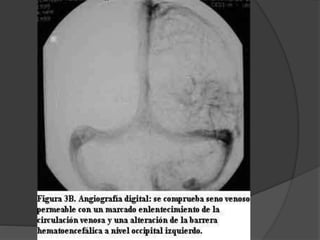

Enfermedad de Sturge-Weber Angiomatosis encefalotrigeminal  Etiopatogenia desconocida  Mas frecuente dentro de los sindromes neurocutaneos con predominio de anomalias vasculares.

La lesion fundamentales una malformacion vascular de tipo telangiectasico-venoso que afecta:  la coroides (angioma coroideo)  la cara (angioma facial)  el cerebro (angioma leptomeningeo) Puede ser del mismo lado, bilateral o presentarse inclompleto. Mancha en vino de oporto

Otras afecciones  Buftalmos Glaucoma  Epilepsia  Calcificaciones cerebrales  Retraso mental  Hemianopsia  Hemiparesia